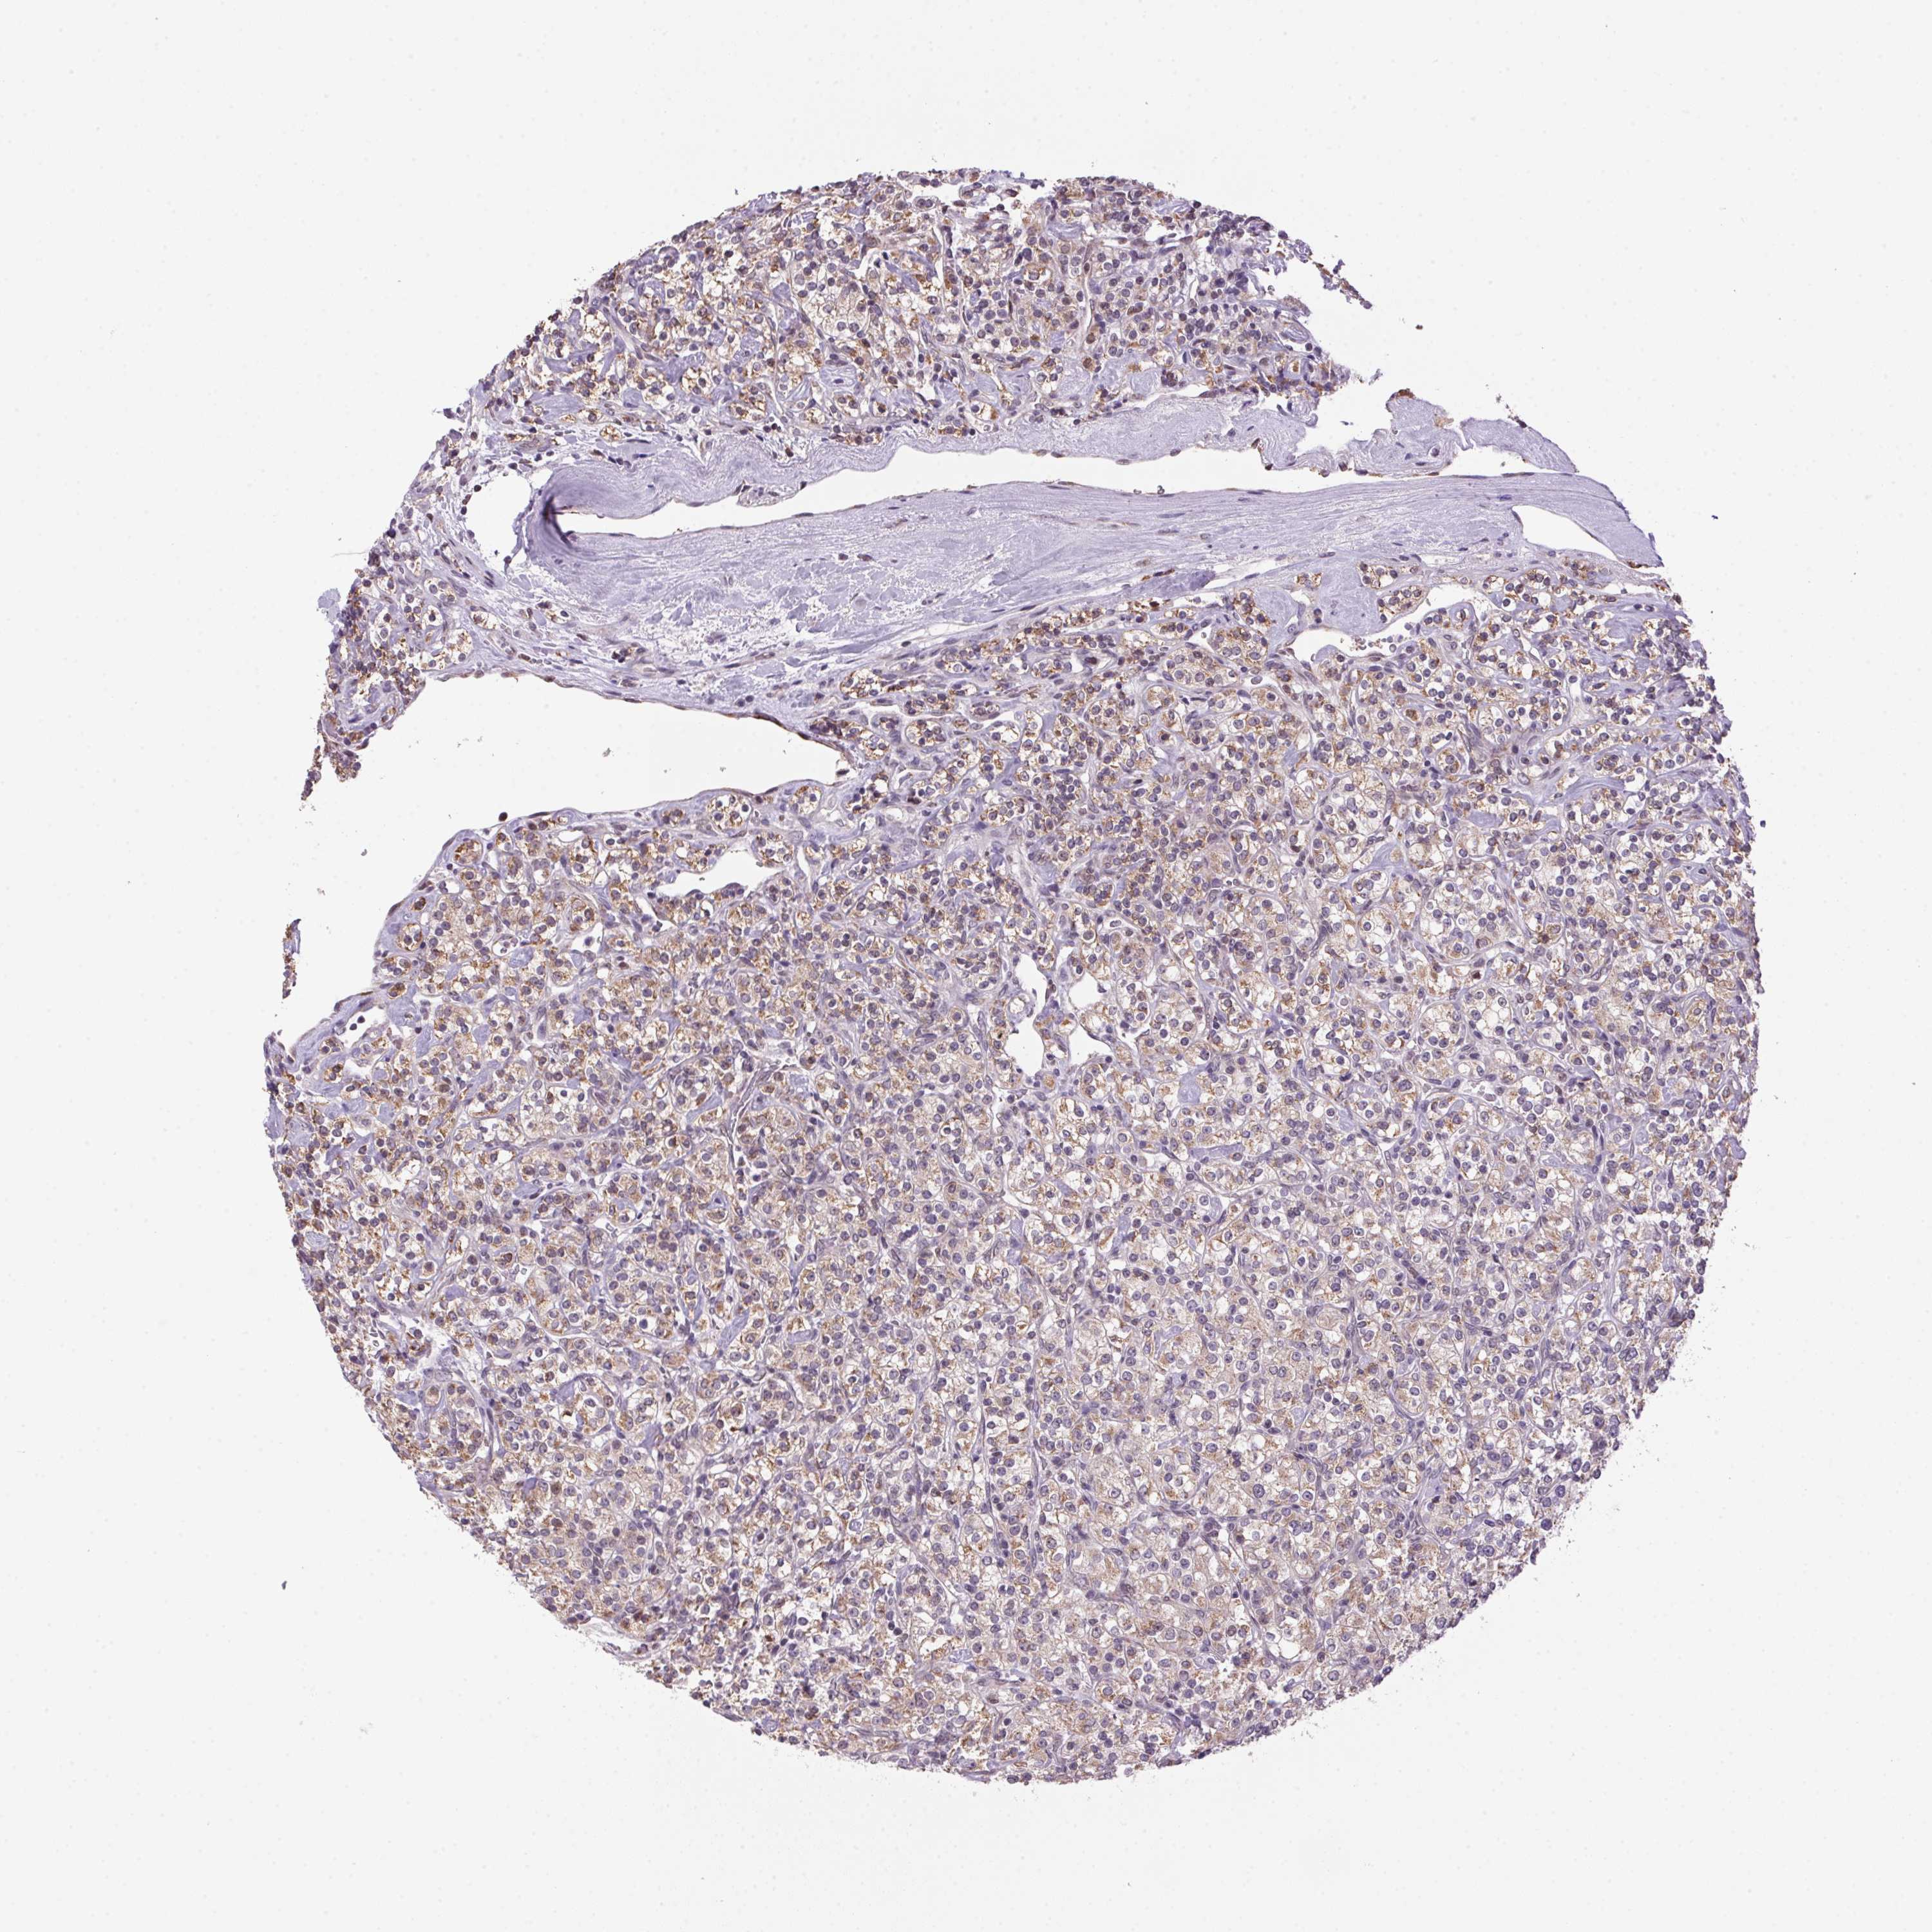

KIDNEY RENAL CLEAR CELL CARCINOMA (VALIDATION) - Interactive survival scatter ploti

The Survival Scatter plot shows the clinical status (i.e. dead or alive) for all individuals in the patient cohort, based on the same data that underlies the corresponding Kaplan-Meier plots. Patients that are alive at last time for follow-up are shown in blue and patients who have died during the study are shown in red.

The x-axis shows the expression levels (FPKM) of the investigated gene in the tumor tissue at the time of diagnosis. The y-axis shows the follow-up time after diagnosis (years). Both axes are complimented with kernel density curves demonstrating the data density over the axes. The top density plot shows the expression levels (FPKM) distribution among dead (red) and alive patients (blue). The right density plot shows the data density of the survived years of dead patients with high and low expression levels respectively, stratified using the cutoff indicated by the vertical dashed line through the Survival Scatter plot. This cutoff is automatically defined based on the FPKM cutoff that minimizes the p-score. The cutoff can be changed by dragging the vertical line or by entering a cutoff value in the square labeled "Current cut-off".

Under the Survival Scatter plot the p-score landscape (black curve; left axis) is shown together with dead median separation (red curve; right axis). Dead median separation is the difference in median mRNA expression between patients who have died with high and low expression, respectively. It is calculated as follows: median FPKM expression of dead patients with high expression - median FPKM expression of dead patients with low expression. This is intended to aid the user in visually exploring custom cutoffs and the associated p-scores and dead median separation.

Individual patient data is displayed and can be filtered by clicking on one or more of the category buttons on the top of the page. Categories describing expression level and patient information include: high, low, alive, dead, female, male and tumor stages. The scale of the x-axis can be toggled between linear and log-scale by clicking on the "x log" button. Mouse-over function shows TCGA ID, patient information and mRNA expression (FPKM) for each patient.

& Survival analysisi

Kaplan-Meier plots summarize results from analysis of correlation between mRNA expression level and patient survival. Patients were divided based on level of expression into one of the two groups "low" (under cut off) or "high" (over cut off). X-axis shows time for survival (years) and y-axis shows the probability of survival, where 1.0 corresponds to 100 percent.

AKR1E2 is not prognostic in Kidney Renal Clear Cell Carcinoma (validation)

: 0.96

Average pTPM 1.4

Number of samples 100